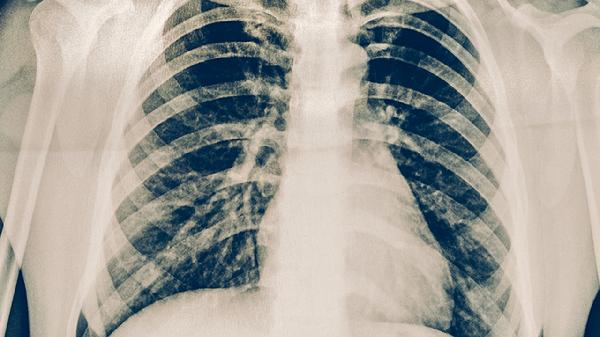

肺結(jié)核病人的早期癥狀主要有咳嗽、咳痰、低熱、盜汗、乏力等。肺結(jié)核是由結(jié)核分枝桿菌感染引起的慢性傳染病,早期癥狀可能較輕且不典型,容易被忽視。

肺結(jié)核患者早期常出現(xiàn)持續(xù)性咳嗽,咳嗽時間超過兩周,初期多為干咳,隨著病情進(jìn)展可能伴有少量黏液痰或膿性痰??人钥赡芘c結(jié)核分枝桿菌感染導(dǎo)致肺部炎癥反應(yīng)有關(guān),炎癥刺激支氣管黏膜引起咳嗽反射。若咳嗽持續(xù)不緩解或加重,建議及時就醫(yī)進(jìn)行胸部影像學(xué)檢查和痰結(jié)核菌檢查。

肺結(jié)核早期癥狀多樣且不典型,若出現(xiàn)上述癥狀持續(xù)兩周以上,特別是咳嗽、低熱、盜汗等癥狀組合出現(xiàn)時,應(yīng)及時到呼吸內(nèi)科或感染科就診。確診肺結(jié)核后應(yīng)遵醫(yī)囑規(guī)范使用抗結(jié)核藥物,常用藥物包括異煙肼片、利福平膠囊、吡嗪酰胺片、乙胺丁醇片和鏈霉素注射液等。治療期間應(yīng)注意加強(qiáng)營養(yǎng),保證充足休息,避免勞累,定期復(fù)查評估治療效果。同時應(yīng)注意呼吸道隔離,避免傳染他人,咳嗽或打噴嚏時用紙巾遮掩口鼻,痰液應(yīng)消毒處理。